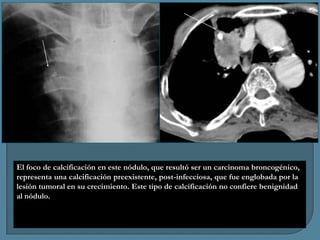

El foco de calcificación en este nódulo, que resultó ser un carcinoma broncogénico,

representa una calcificación preexistente, post-infecciosa, que fue englobada por la

lesión tumoral en su crecimiento. Este tipo de calcificación no confiere benignidad

al nódulo.